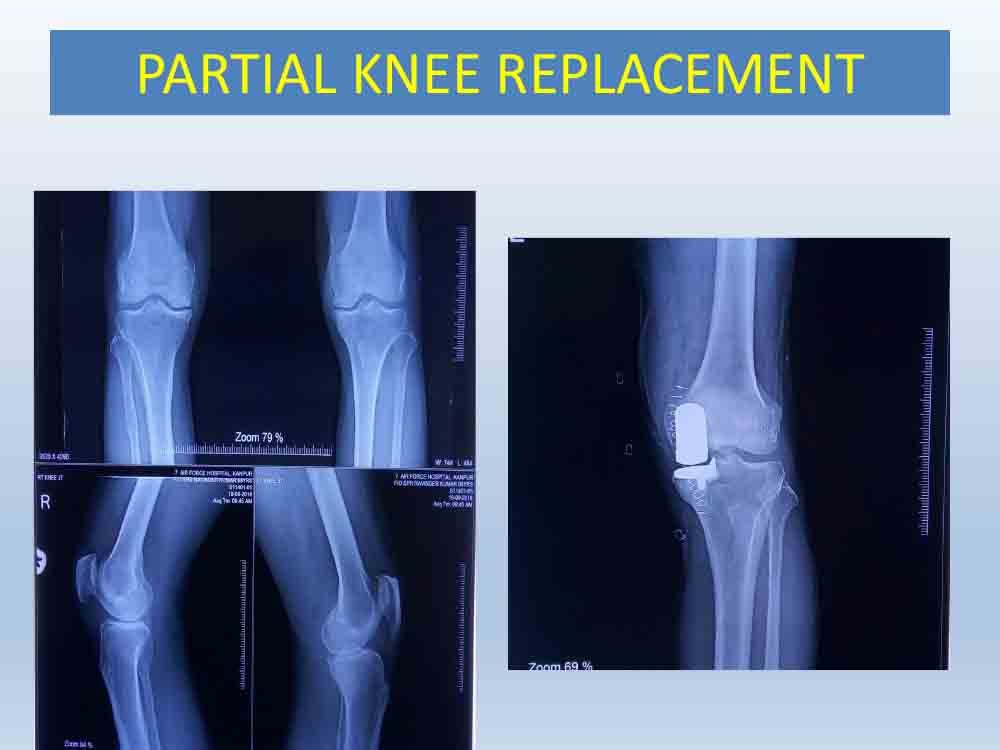

What is Partial Knee Replacement ?

In some patients who are more than 70 years of age and have limited arthritis of the knee joint, the whole knee need not be replaced. Only the diseased portion is removed, surfaces are reshape and metal with plastic are inserted with bone cement of those part which have been removed.